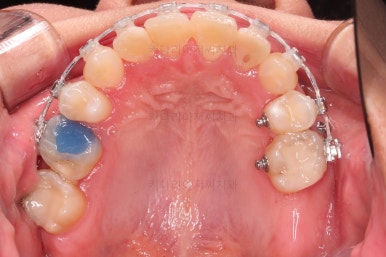

초진 시 입안의 모습입니다.

하지만 이번 환자분은 매우 삐뚠 앞니쪽에 충치가 있었기 때문에 급한대로 신경치료만 하고 임시로 떼워놓고 가지런하게 된 뒤에 최종적으로 심미보철을 진행하기로 했습니다.

현재 모습대로 보철을 한다면, 공간부족으로 치아 크기가 예쁘게 안나오고 삐둔 형태대로 모양이 만들어져서 자칫하면 가지런하게 된 뒤에 모양이 매우 못나 보일 수 있기 때문이죠.

충치치료르 한다고 몇 달을 기다리다 보면 교정 후에 해야 하는 충치는 더 늦어지기 때문에 우선 교정장치부터 부착하고 충치치료는 병행해 가면서 하기로 했습니다.

윗니 앞니는 급한대로 신경치료 부터 진행했고, 최종 심미보철은 교정 후 미루었습니다.